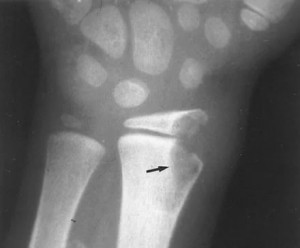

От общего числа всех заболеваний, связанных с палочкой Коха, на туберкулез костей и суставов приходится 3,4%. Тем не менее именно кости являются наиболее распространенным местом данной инфекции, после легких. Чаще всего туберкулез костей поражает позвоночник. Так происходит в 40% случаев. Далее по 20% отводится на коленный и тазобедренный суставы. А вот диагностировать туберкулез других частей тела, врачам доводится достаточно редко.